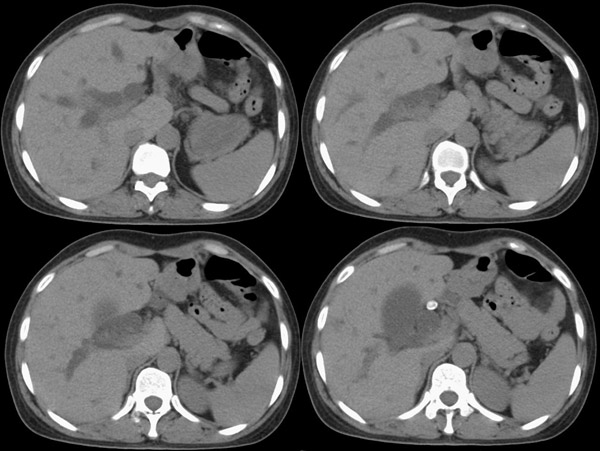

胆总管矢状及冠状重建:

行胆囊切除术及胆总管探查术:探查见肝脏大小正常,肝缘稍钝,肝表面光整,胆囊大小12*3*3cm3,壁水肿增厚约0。5cm,张力稍高,胆囊与大网膜呈纤维粘连;胆总管宽约2cm,壁明显增厚,触摸胆总管,隐约可触及一条状物,于胆总管做一长约1、5cm的纵行切口,用取石钳在胆总管内取出一条长约16cm长黑色的长条状物,较脆易折断,宽约0、6cm,证实为蛔虫尸体。用探子往下探,未发现下端结石最后诊断:胆道蛔虫症继发胆系梗阻性扩张。

疑惑:1、ct表现胆总管下端有结石影,但手术中未发现???

2、胆总管下端若是阳性结石,那么这条16*0、6cm2的大蛔虫是如何进入胆总管的?!

结合胆道蛔虫病史,蛔虫性胆系结石并胆系梗阻能明确诊断。至于说没有发现胆总管下端阳性结石,因为已经取出来了。